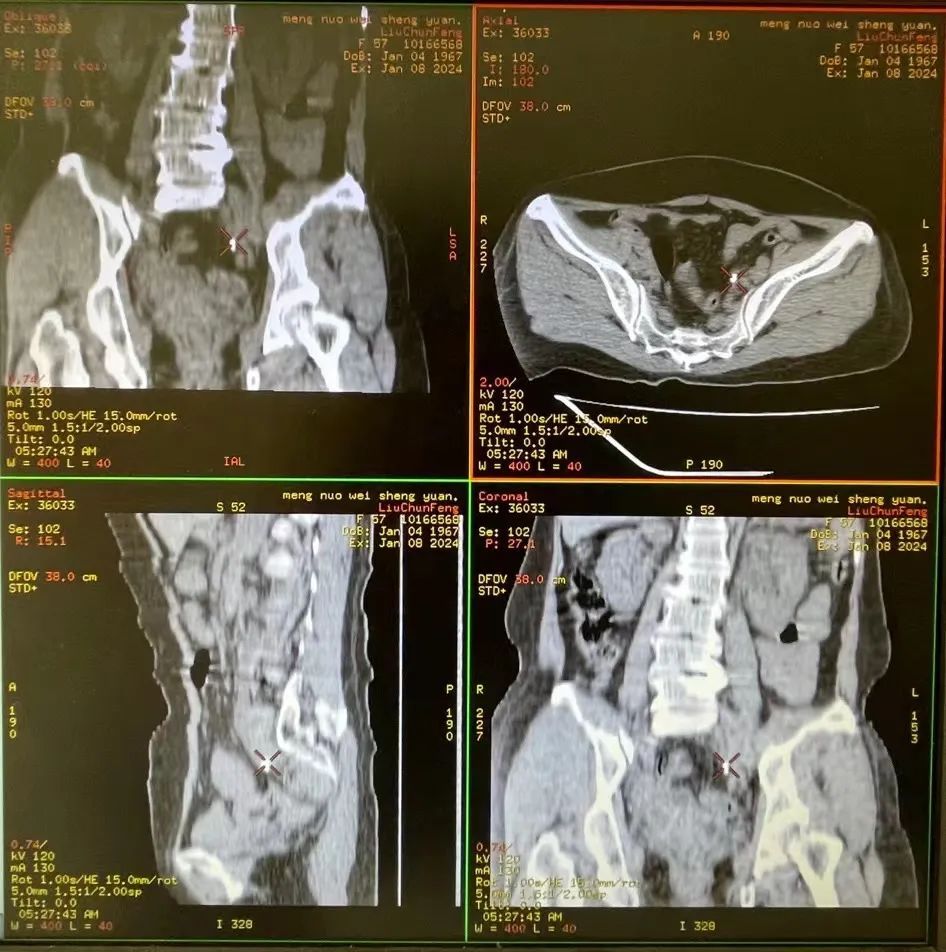

据了解,患者女性,57岁,因左侧腰腹部剧烈疼痛到院区就诊。门诊完善泌尿系CT后以“左输尿管结石伴积水感染”收住院。CT显示左侧输尿管下段可见锥形密度增高结石影,最大层面约为0.6cm*0.5cm,10mm层CT平扫可见2层,左肾盂及左侧输尿管扩张、积水伴感染。